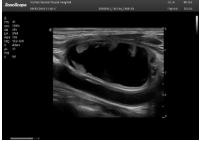

2相控陣探頭

探頭面是平面,接觸面小,近場視野最小,遠場視野大,成像視野呈扇形,適用于心臟。

心臟探頭通常按應(yīng)用人群劃分為成人、兒童、新生兒三類:(1)成人心臟位置最深、搏動速度慢;(2)新生兒心臟位置較淺、搏動速度最快;(3)兒童心臟的情況介于新生兒與成人之間。

肥厚性心肌病-心尖四腔